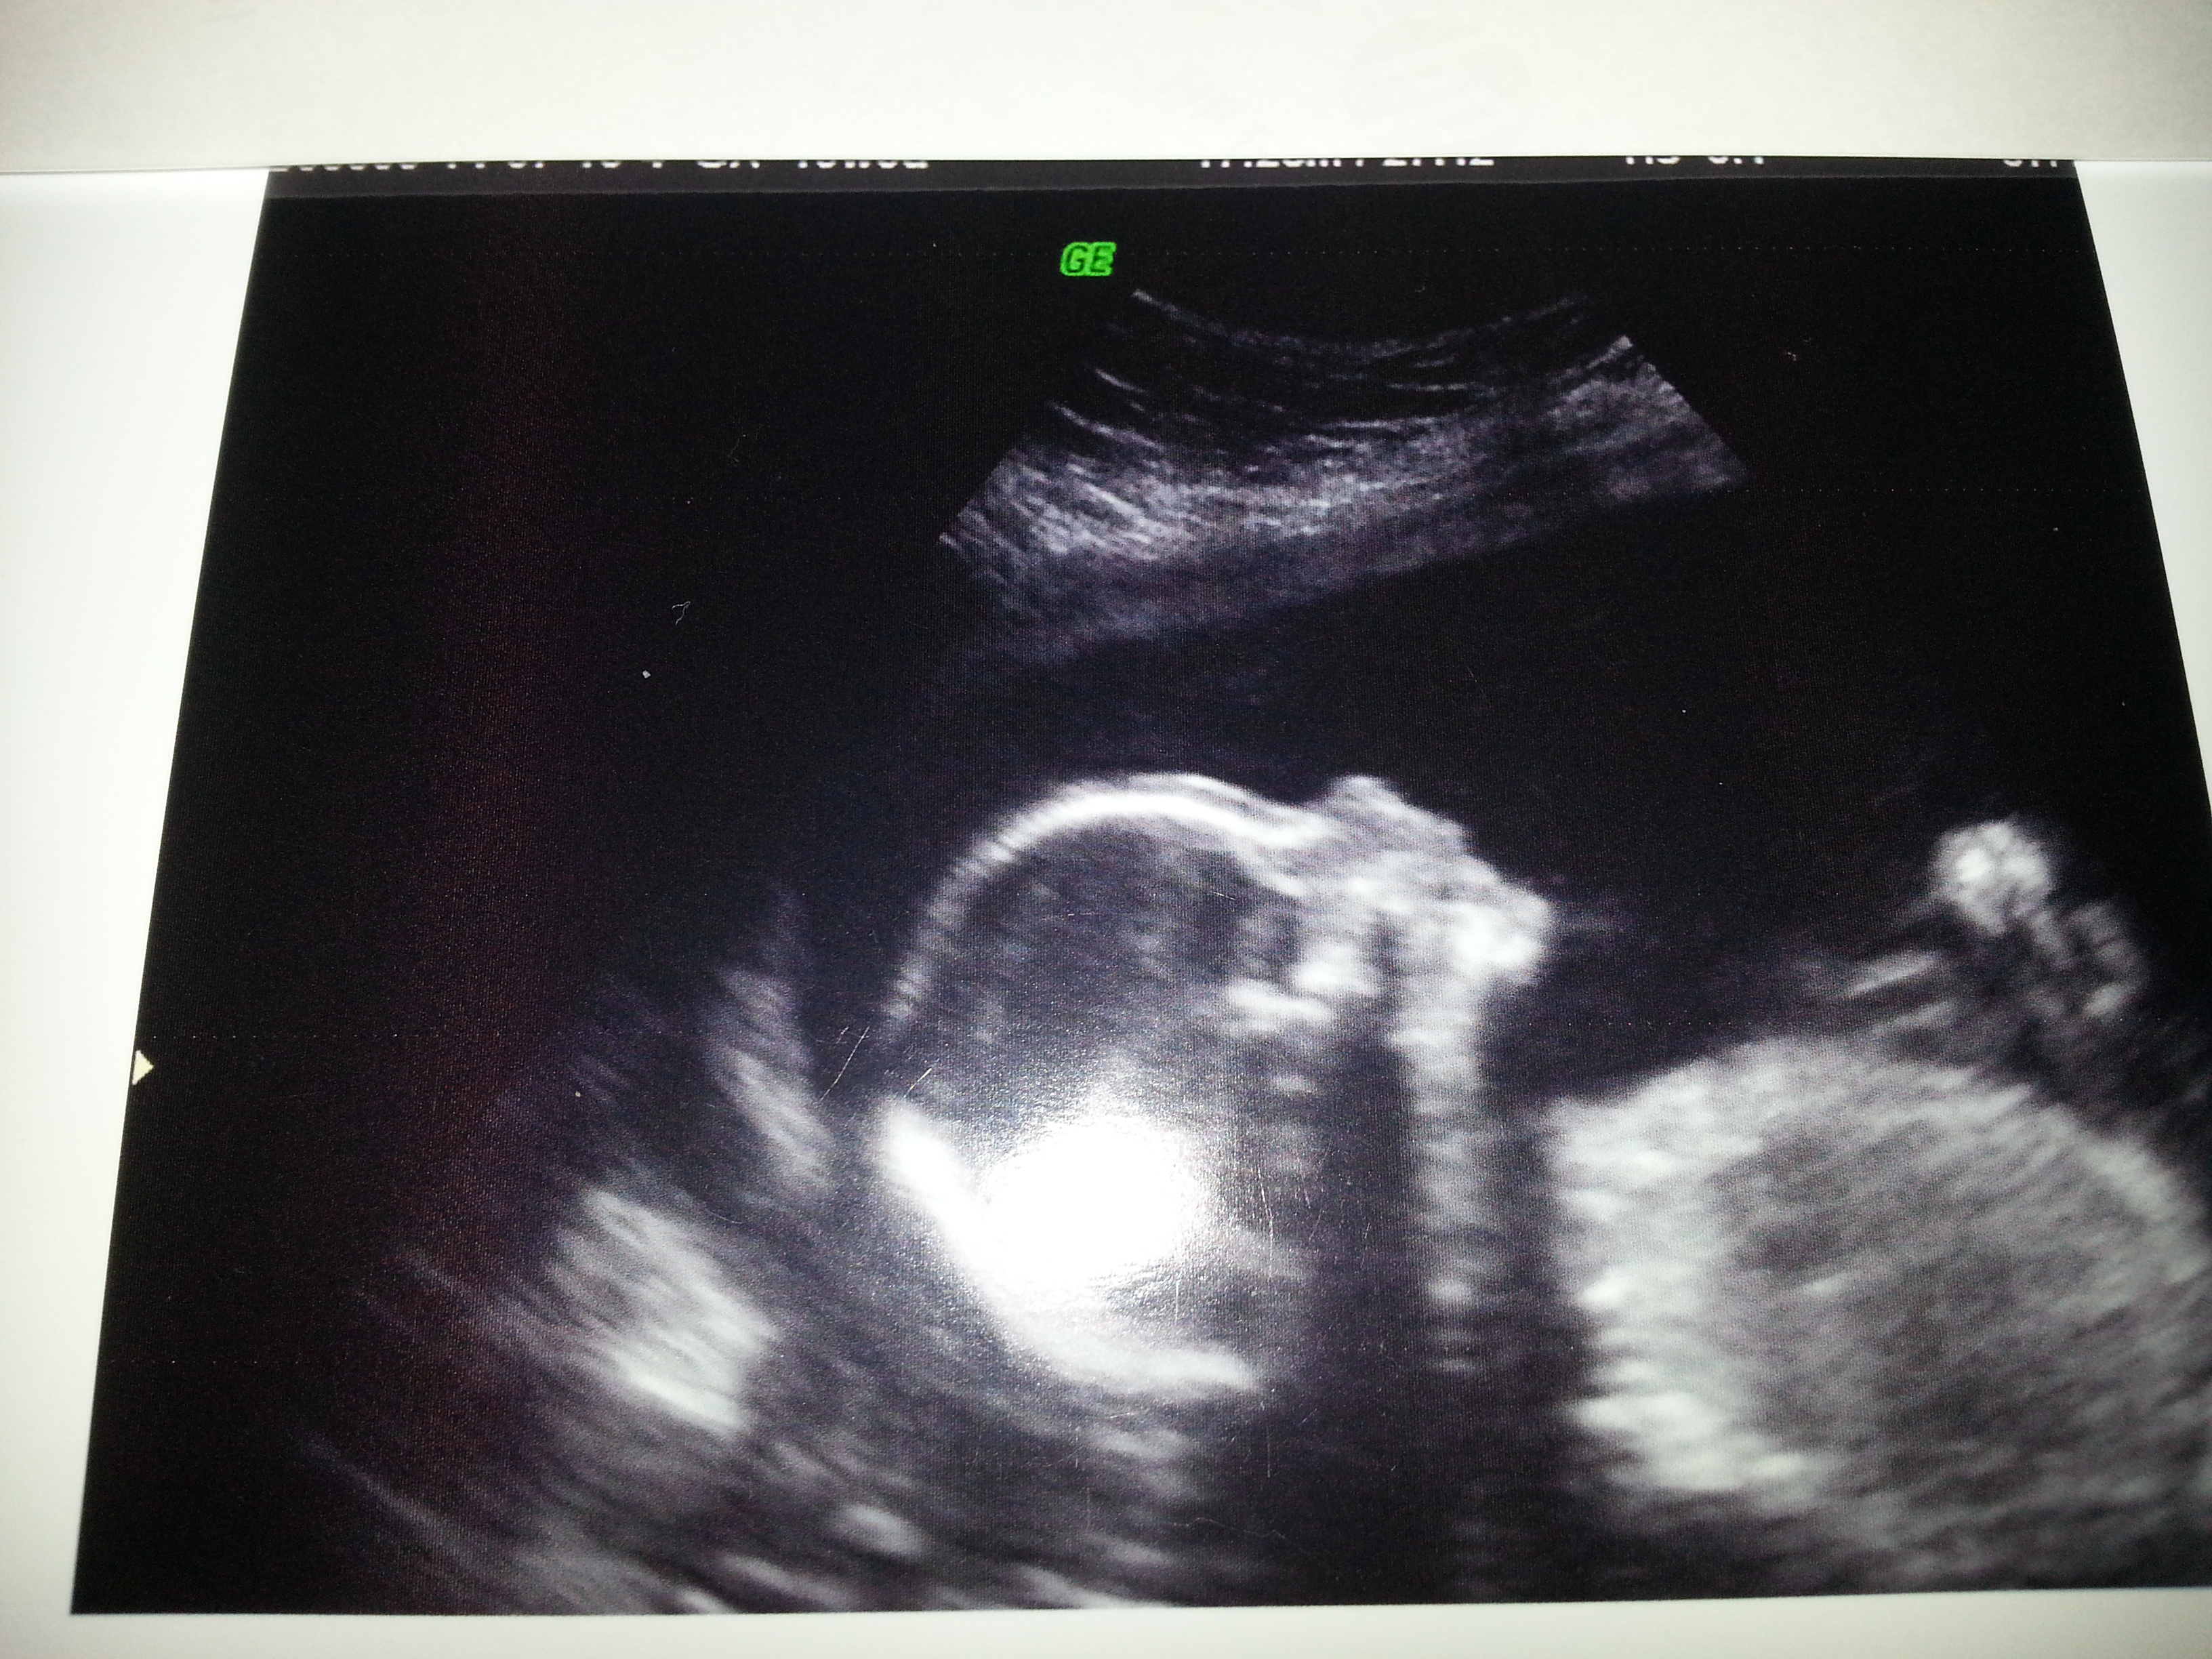

TJ1979 said:I totally thought he was going to be a she! But I'm usually always wrong. Congrats! He's adorable.

I totally thought he was going to be a she! But I'm usually always wrong. Congrats! He's adorable.